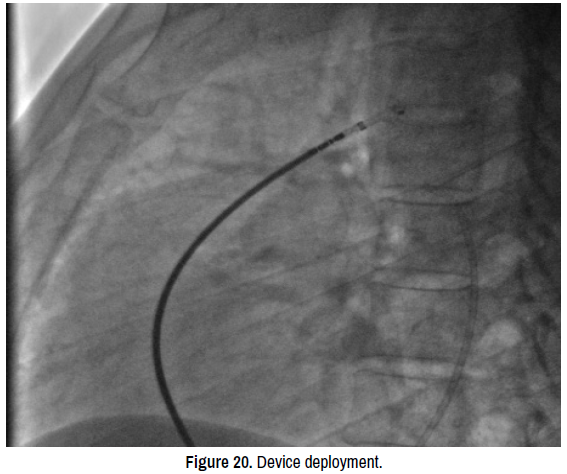

vasculitis-device

Figure 20. Device deployment.

We started the procedure by sedating the child under sevoflutane with a mask and monitoring the heart rate, blood pressure and oxygen saturation. Then we proceeded to rigorous disinfection and establishment of sterile fields and punctured the right femoral artery under local anesthesia with Lidocaine 1% using 5F radial sheath. We then introduced a JR 3.5 5F diagnostic catheter on a 0.035’’ wire to the aortic isthmus and then we opaqued the channel by manual injections of ULTRAVIST 300 contrast to confirm its diameter by angiographic measurement in profile view (4.3 +/- 0.4 mm) (Figure 17). Therefore, we planned to implant a 6/8 PDA Occluder that requires a 7Fr delivery system, for that, we punctured the right femoral vein using 6fr radial sheath and injected Heparin at dose of 100 units per Kg (3000 units) then we crossed the right cavities to the pulmonary artery by a JR 3.5 5Fr diagnostic catheter on 0.035’’ wire. After failing to cross the channel by a straight hydrophilic guide 0.035’’ because of the smallness of the PDA caliber on its pulmonary side we decided to cross it by its aortic side with the hydrophilic straight 0.035’’ 260 cm wire that we exteriorized from the left JR 3.5 5Fr diagnostic catheter through the JR 3.5 5Fr diagnostic catheter mounted on the right on which we introduced the delivery system 7F by the right femoral venous access (Figure 18). The delivery system being placed from the femoral vein to the right cavities and then through the canal to the aortic isthmus, the prosthesis is debubbled and fixed by screwing on its rod then mounted in its chamber (room) under serum washing and conveyed to the end of the 7F sheath (Figure 19). We deployed the distal part of the device in the aortic isthmus and pulled back the entire system to the aortic ampulla under angiographic control (Figure 20). A traction was, then, maintained on the rod with removal of the 7Fr sheath until the device was completely deployed into the body of the channel, injections through the JR3.5 5F catheter placed in the aorta were performed close to the device confirming its correct positioning in the aortic ampulla and absence of residual shunt, comforted by an echocardiographic control (Figure 21). We proceeded to the definitive release of the device by an anti-clockwise rotation of the external part of its rod and we ended up with an echocardiographic and angiographic control with contast injection (Figure 22). A final angiographic and ultrasound control was carried out 10 minutes later in Cath Lab before the removal of the material and manual compression of the right femoral artery and vein. The procedure skin to skin took 40 minutes. A compressive bandage was placed for 12 hours. The child was monitored in the awakening room for 2 hours at the end of which she returned to the normal hospital bed.